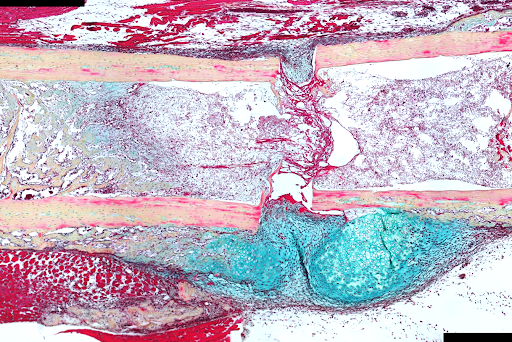

Der Knochen ist ein dynamisches endokrines Organ, das sich ständig umbaut, um die Homöostase zu erhalten, und bei Verletzungen durch einen hoch koordinierten Regenerationsprozess reagiert. Störungen dieser Prozesse – sei es im alltäglichen Knochenumbau oder bei der Frakturheilung – können zu Funktionsverlust, chronischen Schmerzen und verminderter Lebensqualität führen. Das Verständnis der zugrunde liegenden Regulationsmechanismen ist daher entscheidend für Fortschritte in der Knochengesundheit.

Unsere Forschung konzentriert sich auf die Aufklärung der Rolle der Glukokortikoidrezeptor-Signalgebung in skelettalen Stamm- und Vorläuferzellen sowohl während der Knochenregeneration als auch in der Homöostase. Darüber hinaus untersuchen wir die Mikroumgebung der Stammzellnische im Knochen und entwickeln alternative in vitro-Modelle für die Knochenforschung. Unser integrativer Ansatz eröffnet neue Perspektiven und schafft die Grundlage für die Identifizierung neuartiger therapeutischer Zielstrukturen zur Verbesserung der Knochenhomöostase und Frakturheilung.

Lee S, Remark LH, Josephson AM, Leclerc K, Lopez EM, Kirby DJ, Mehta D, Litwa HP, Wong MZ, Shin SY, et al. Npj Regen. Med. 2021;6:29. doi: 10.1038/s41536-021-00139-x